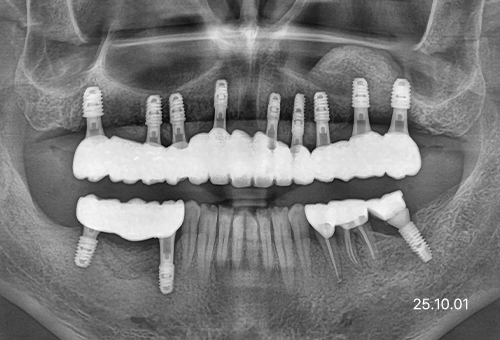

임플란트 주위염 등으로

임플란트 재수술이 필요한 경우

기존 임플란트 주변의 염증이나 문제로 재수술이 필요한 경우, 전문적인 진단과 시술을 통해 기능을 다시 회복할 수 있습니다.